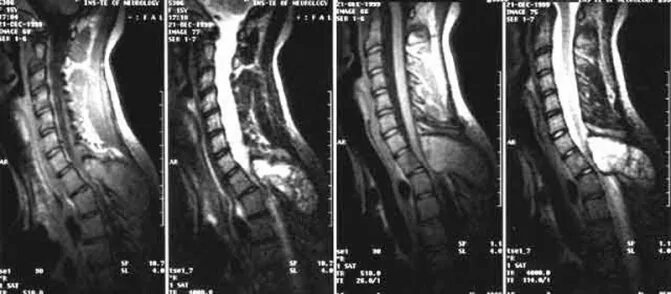

Киста в грудном отделе позвоночника